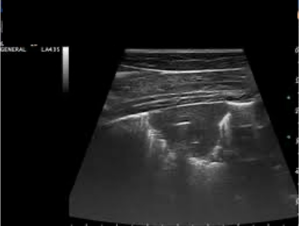

Du tilkaldes til et 10 dage gammelt føl, som er akut halt på venstre bagben grad 4/5 og med tempratur 39,5 celcius. Ved din kliniske undersøgelse finder du en mild ødematøs hævelse omkring venstre tarsus. Du udtager et ledaspirat fra tarso-kruralled og får følgende resultat: Totalprotein: 20 g/l. Celletal: 15.000/uL med 75% neutrofile. Hvordan vil du videre fortsætte?

1 Scintigrafi

2 Røntgenbillede

3 Metacam og boksro

4 Blodkultur

Det rigtige svar er 2